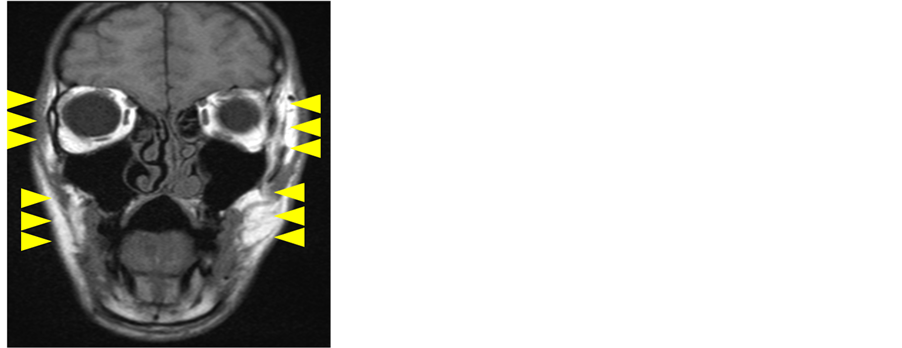

Preoperative extraoral examination showed reversed occlusion and deformation of the facial appearance (Figure 1, Figure 2). In addition, constriction bands and deformation of the limbs were identified (Figure 3). Preoperative intraoral findings exhibited the angle class two malocclusion and severe skeletal open bite (Figure 2). The patient could not speak his lines smoothly and maintain a closed position of the jaws due to weakness of the masticatory muscles. Preoperative cephalometric analysis showed poor growth of the maxilla and false mandibular prognathism (Table 1). MRI showed atrophy of the masticatory muscles (Figure 4). Severe muscle weakness induced poor development of the mandibular ramus, resulting in severe open bite (Figure 5). We therefore attempted to achieve functional recovery using muscle function therapy pre- and postoperatively. We performed Lefort type I osteotomy and mandibular sagittal splitting osteotomy under general anesthesia in May 2010. We placed two bone screws on the maxilla and mandible and performed inter-maxillary fixation for 1 week from postoperative day 2. Since preservation of the teeth was a key consideration, ideal overbite was not apparent on postoperative intraoral examination. With the release of intermaxillary fixation, occlusion was not stable. We performed objective therapeutic evaluations before and after surgery using electromyography (EMG) and tests of masticatory and language functions.

Figure 4. Postoperative MRI shows atrophy and poor development of bilateral masticatory muscles.

patient showed dysfunction of the masticatory muscles on the initial visit to our hospital and we conducted functional recovery therapy for muscle function both before and after surgery. We evaluated the therapeutic effects objectively pre- and postoperatively using EMG and tests of masticatory and language functions. EMG results showed no significant change between before and after surgery. Preoperative functional score was 10%, improving to 45% after surgery (Table 2). With the Japanese 100-syllable intelligibility speech test, the overall percentage of correct answers improved from 22.4% to 26.4%. In terms of articulation, sibilant, alveolar and velar sounds were the most improved (Table 3). Results of the conversation intelligibility test improved from 3.6 preoperatively to 2.8 postoperatively. Craniofacial morphology improved with the 2-jaw osteotomy, but the patient did not achieve adequate functional recovery. This was attributed to poor growth and atrophy of the masticatory muscles as seen on MRI. Sufficient activation of the muscles of mastication in rehabilitation may not be achievable beyond a certain threshold of atrophy. Because the maxillofacial skeleton was improved with orthgnathic surgery, postoperative function of the surrounding masticatory muscles was not improved.